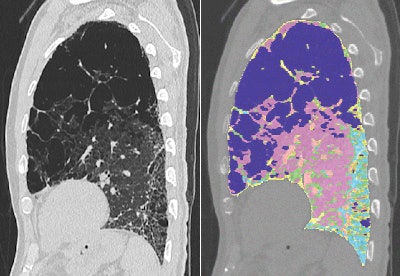

The lung volumes were examined on a computer-aided system that used CT attenuation values to distinguish fibrotic from normal, consolidated, and emphysematous regions on a PC. The automated tool extracts the lung from the CT images using a semiautomated threshold technique. Next, the bronchial trees and blood vessels are removed.

The algorithm categorized the lungs pixel by pixel, and then calculated the relative volume of each lesion to the CT lung volume as "normal(%)," "ground-glass opacities(%)," "consolidation(%)," "emphysema(%)," and "fibrosis(%)."